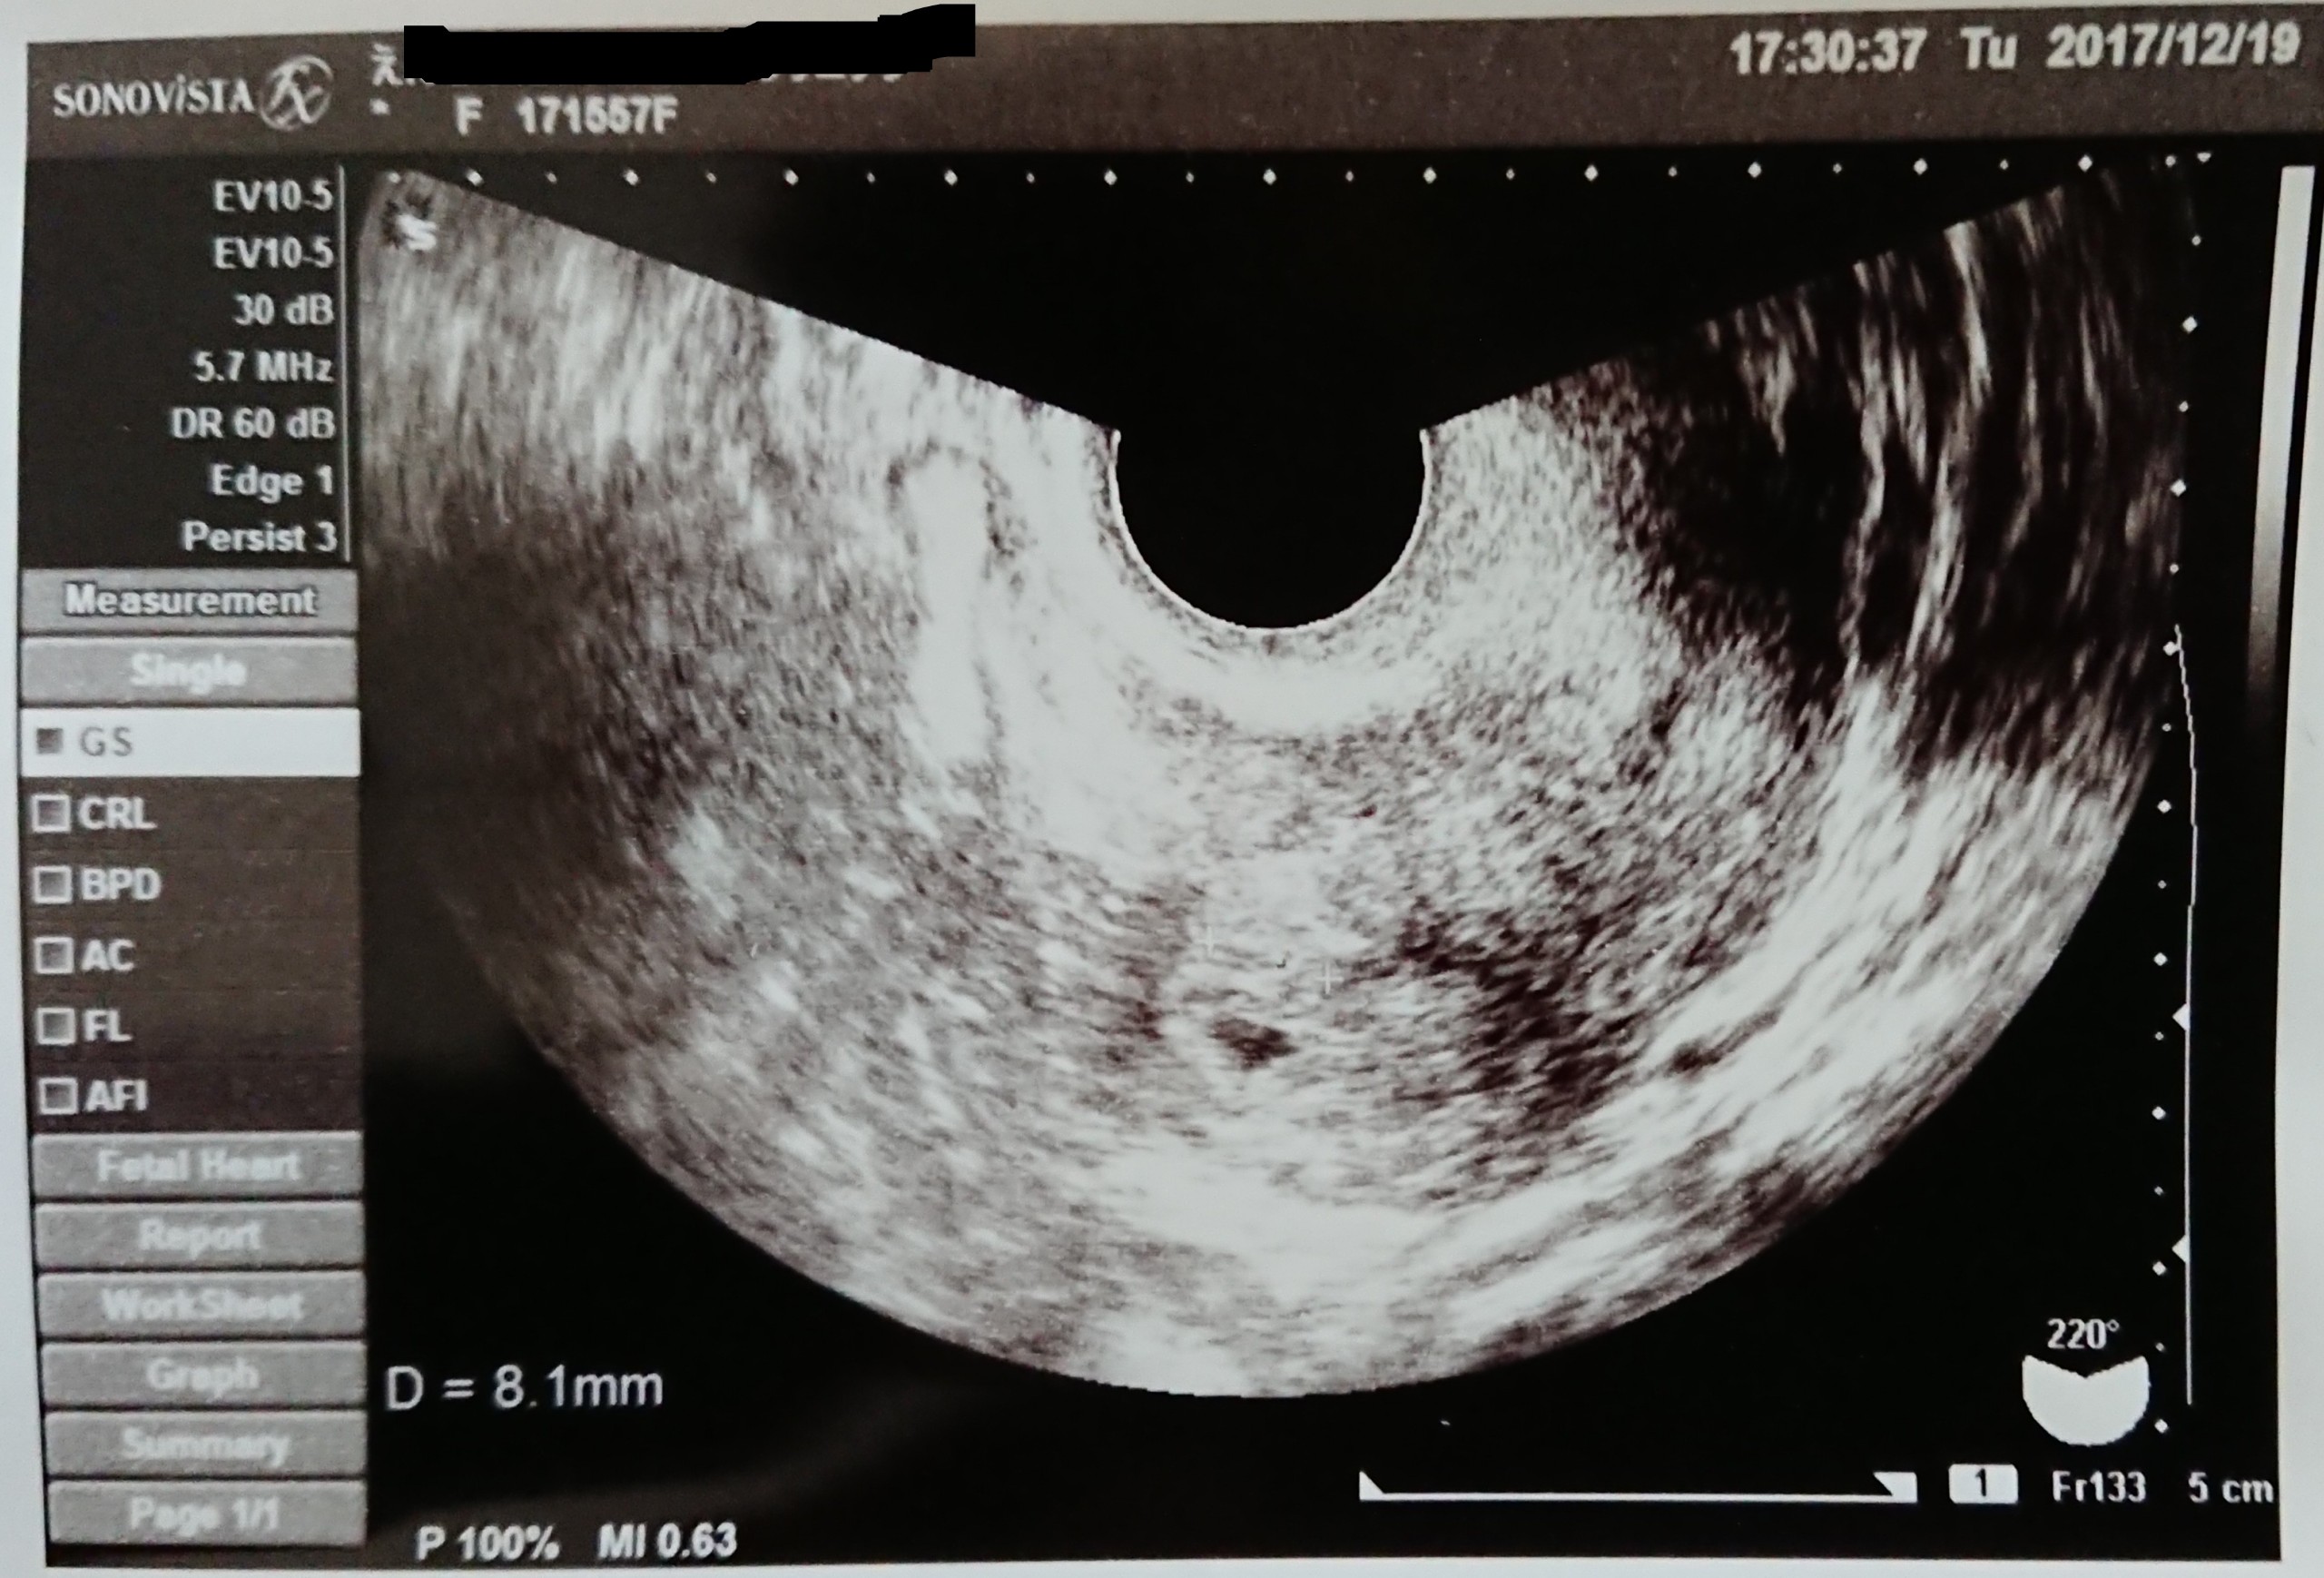

妊娠5週0日 5w0d の超音波 エコー 写真

妊娠5週 0 2日 のエコー写真 体験談

妊娠5週 0 2日 のエコー写真 体験談

妊娠5週0日 5w0d の超音波 エコー 写真

妊娠5週0日 5w0d の超音波 エコー 写真

妊娠5週 0 2日 のエコー写真 体験談